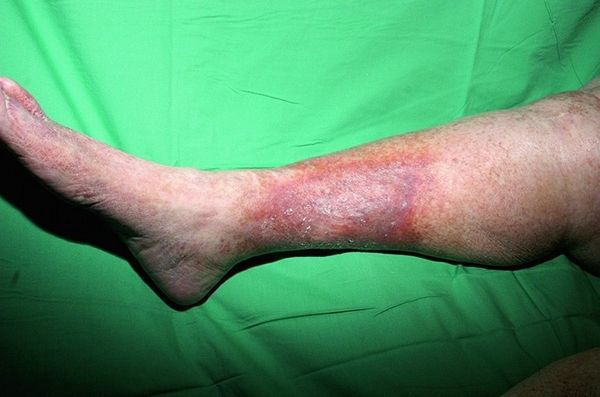

Панникулит (Panniculitis) — это группа различных по причине заболеваний, при которых воспаляется подкожная жировая клетчатка и в ней образуются болезненные на ощупь уплотнения. Эти узлы могут сливаться и иногда вскрываться с выделением пенистой массы. Также в патологический процесс могут вовлекаться внутренние органы и опорно-двигательная система.

Основной симптом всех панникулитов — это болезненные на ощупь уплотнения (узлы) в подкожной жировой клетчатке. Их размеры, количество и расположение могут различаться при разных формах заболевания. Чаще всего они появляются на ногах и руках, иногда на задней поверхности туловища, животе, груди, лице или ягодицах [5].